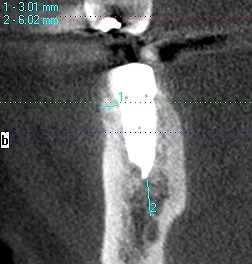

術前のCTになります

5mmの11,5mmというインプラントを埋入しています